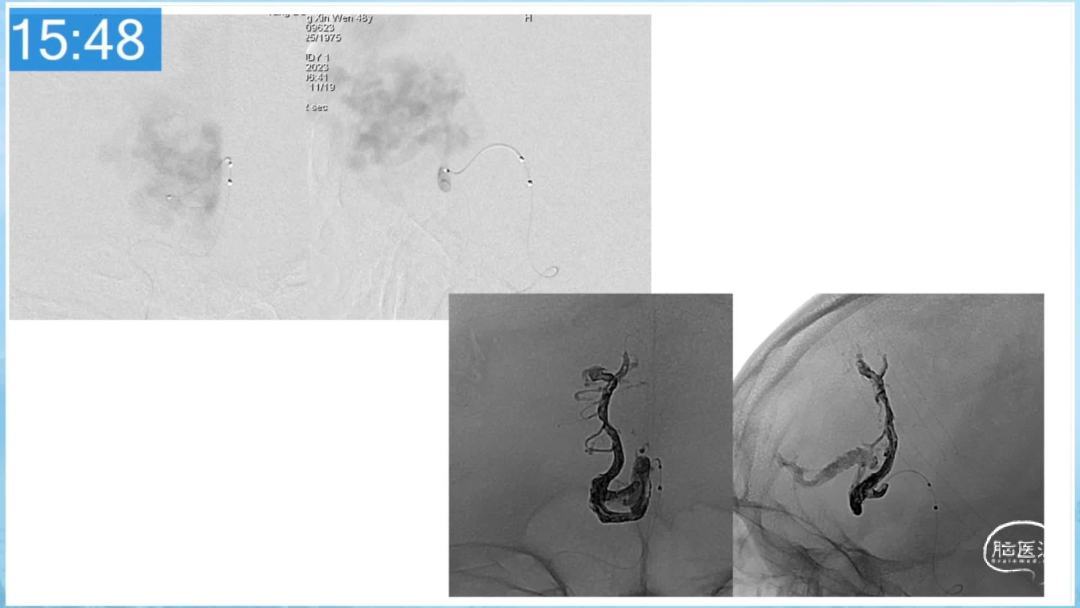

合理的复合平台下的综合治疗,针对每一个病变对应不同方法安全性分析,不预设、不排斥,每种技术发挥到最佳,互相保障。

本期为大家特别分享:空军军医大学唐都医院邓剑平教授的精彩会议内容《颅内动静脉畸形的复合手术治疗》,欢迎大家阅读和分享!